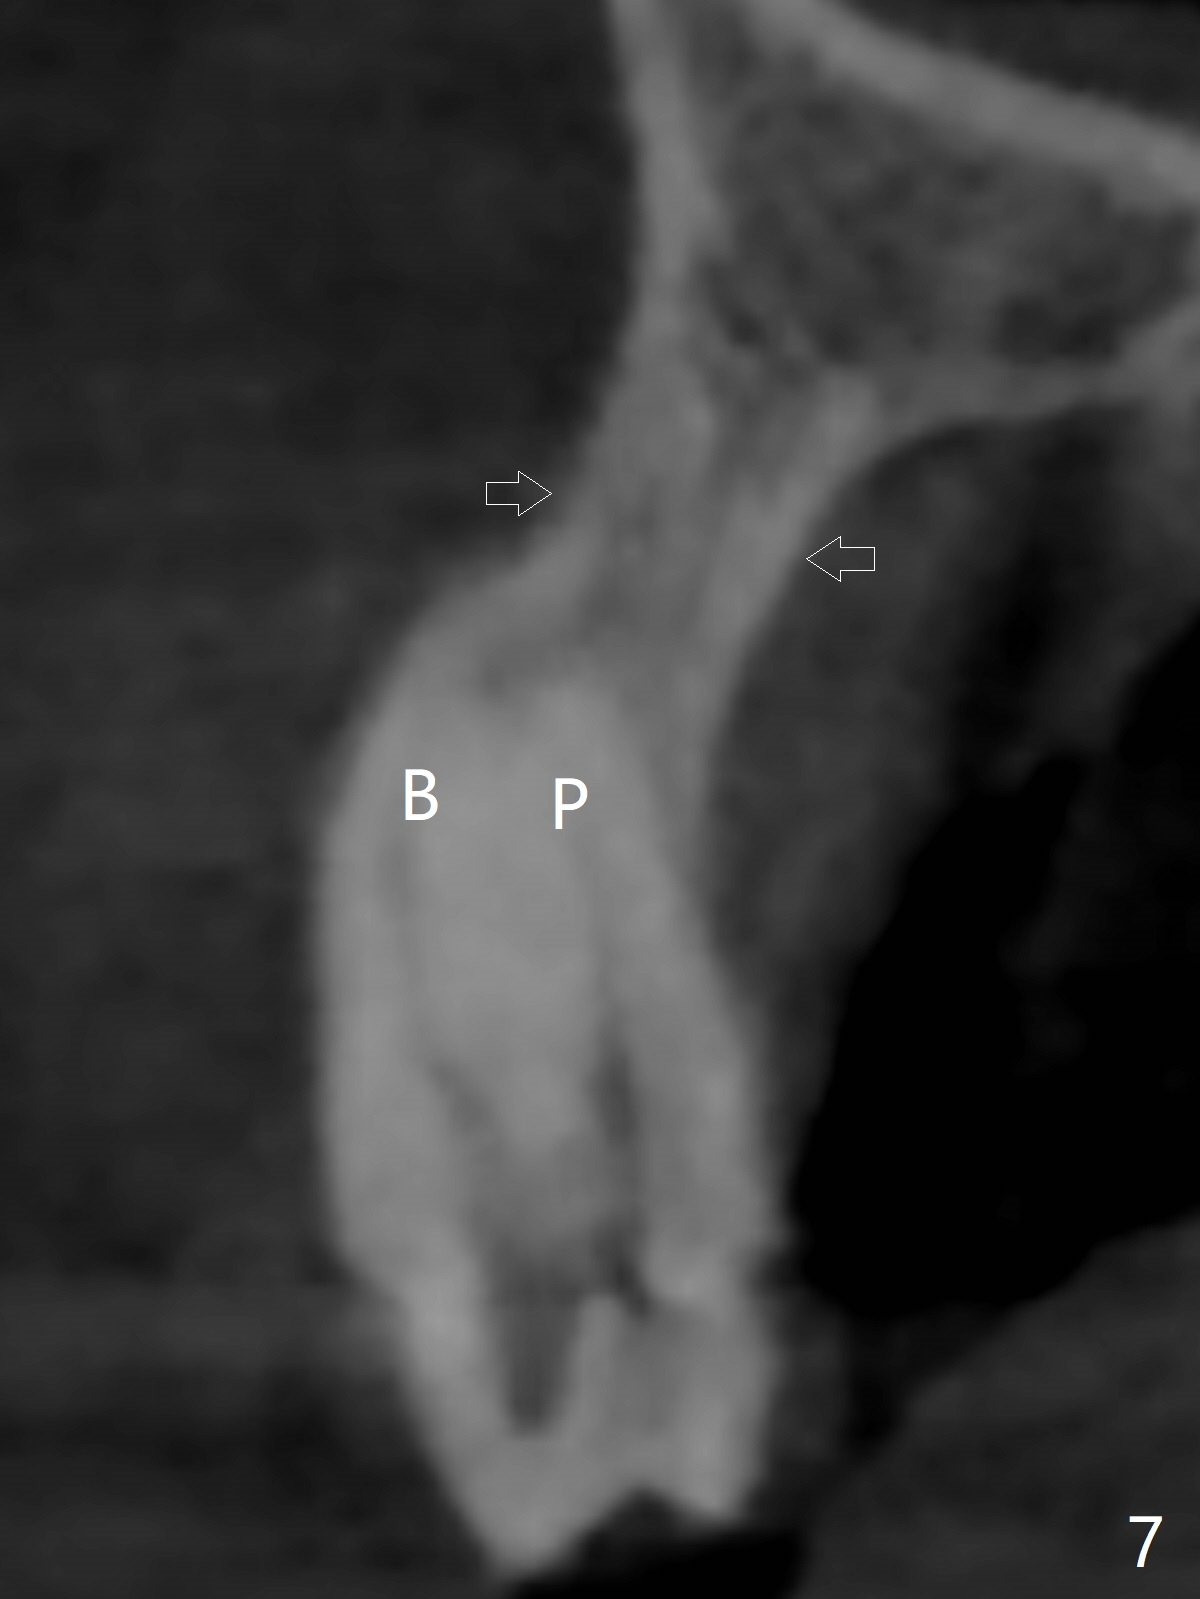

A 51-year-old woman lost the teeth #6 and 7 due to odontoma removal ~30 years ago. The area was restored with a FPD. The latter is removed with immediate implant at #8 8-9 months earlier. Particulate bone graft does not repair the bone deficiency at #6, 7 (Fig.2,3), although the soft tissue looks bulky (Fig.1). It appears that the palatal defect also needs a piece of bone block to fill in (Fig.4). The block will be harvested from the chin (Fig.5,6). If the block graft turns out to be impracticable, the periodontally compromised tooth #5 (bone loss, Fig.2,3,7) will be extracted for immediate implant. Initial osteotomy will be established in the palatal socket (Fig.8,9). Either a 2- (Fig.10) or 1- (Fig.11) piece implant will be placed. After wound healing, impression will be taken for a lab-fabricated provisional FPD.